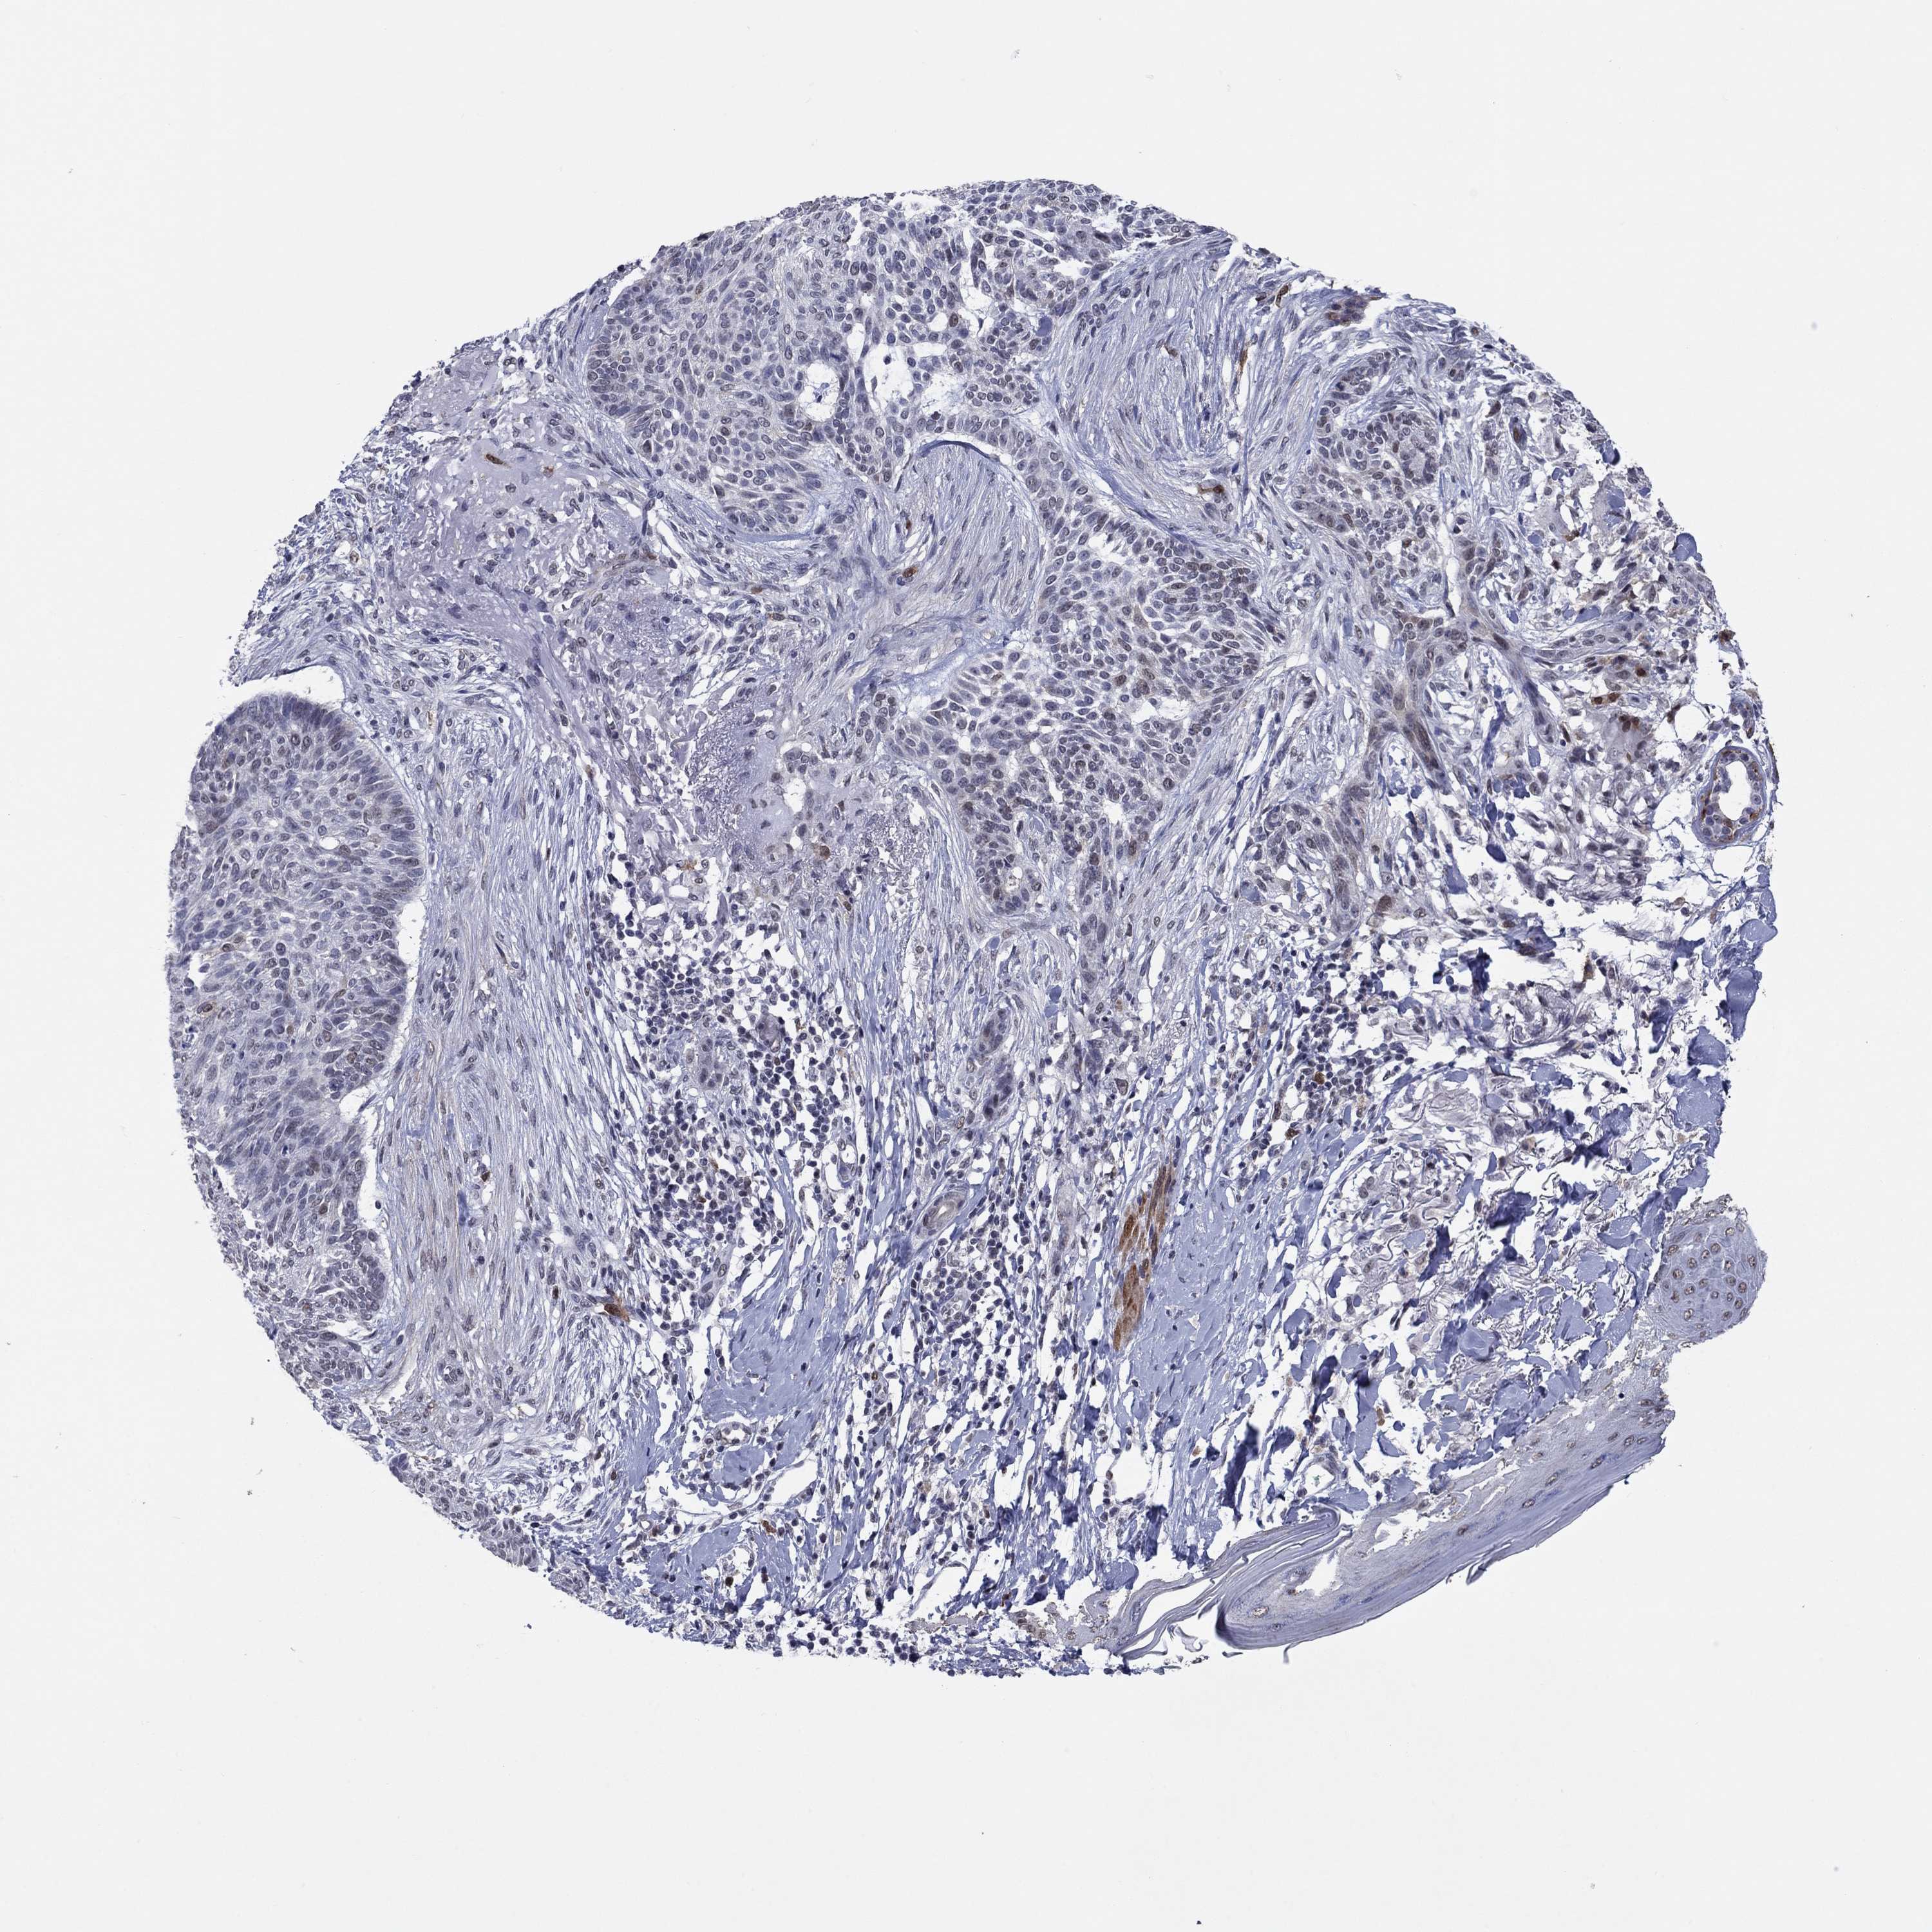

SKIN CANCER - Protein expressioni

A mouse-over function shows sample information and annotation data. Click on an image to view it in a full screen mode. Samples can be filtered based on level of antibody staining by selecting one or several of the following categories: high, medium, low and not detected. The assay and annotation is described here.

Antibody stainingi

Antibody staining in the annotated cell types in the current human tissue is reported as not detected, low, medium, or high, based on conventional immunohistochemistry profiling in selected tissues. This score is based on the combination of the staining intensity and fraction of stained cells.

Each image is clickable and will lead to virtual microscopy that enables deeper exploration of all samples and also displays staining intensity scores, fraction scores and subcellular localization as well as patient and tissue information for each sample.

Antibody HPA074922

Antibody CAB002784

Basal cell carcinoma

Squamous cell carcinoma, NOS